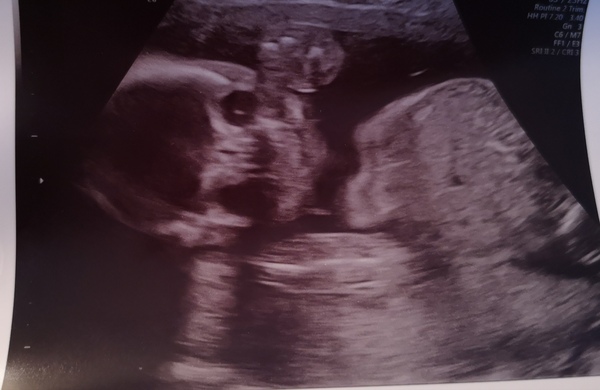

Just back from our 20 week scan, all looked fine. Baby was facing us so we have a couple of fairly terrifying face on pictures, which look pretty appropriate for upcoming Halloween decorations! πŸ˜‚ Also one nice profile one though and a cute one of its little feet. It was so active in there, playing with its toes and bouncing up and down. Made it difficult for the sonographer to get some measurements as it was moving so much, but managed in the end. Very, very relieved and feel like I can start to get a bit more excited now as it all seems a bit more real!

Congrats on a lovely scan @toastfiend can we see some pics? I ask because I've heard about these terrifying 'face forward' pictures and I'm just sheer intrigued as to what they look like πŸ˜‚

@ballanj just for you, try not to have nightmares, it's genuinely terrifying. To quote my brother in law: "This picture will haunt my dreams..." πŸ˜‚

@toastfiend I live that picture! Ours looked straight on at the 12 week scan and it was freaky. It's like they're peeking into the camera and posing lol.